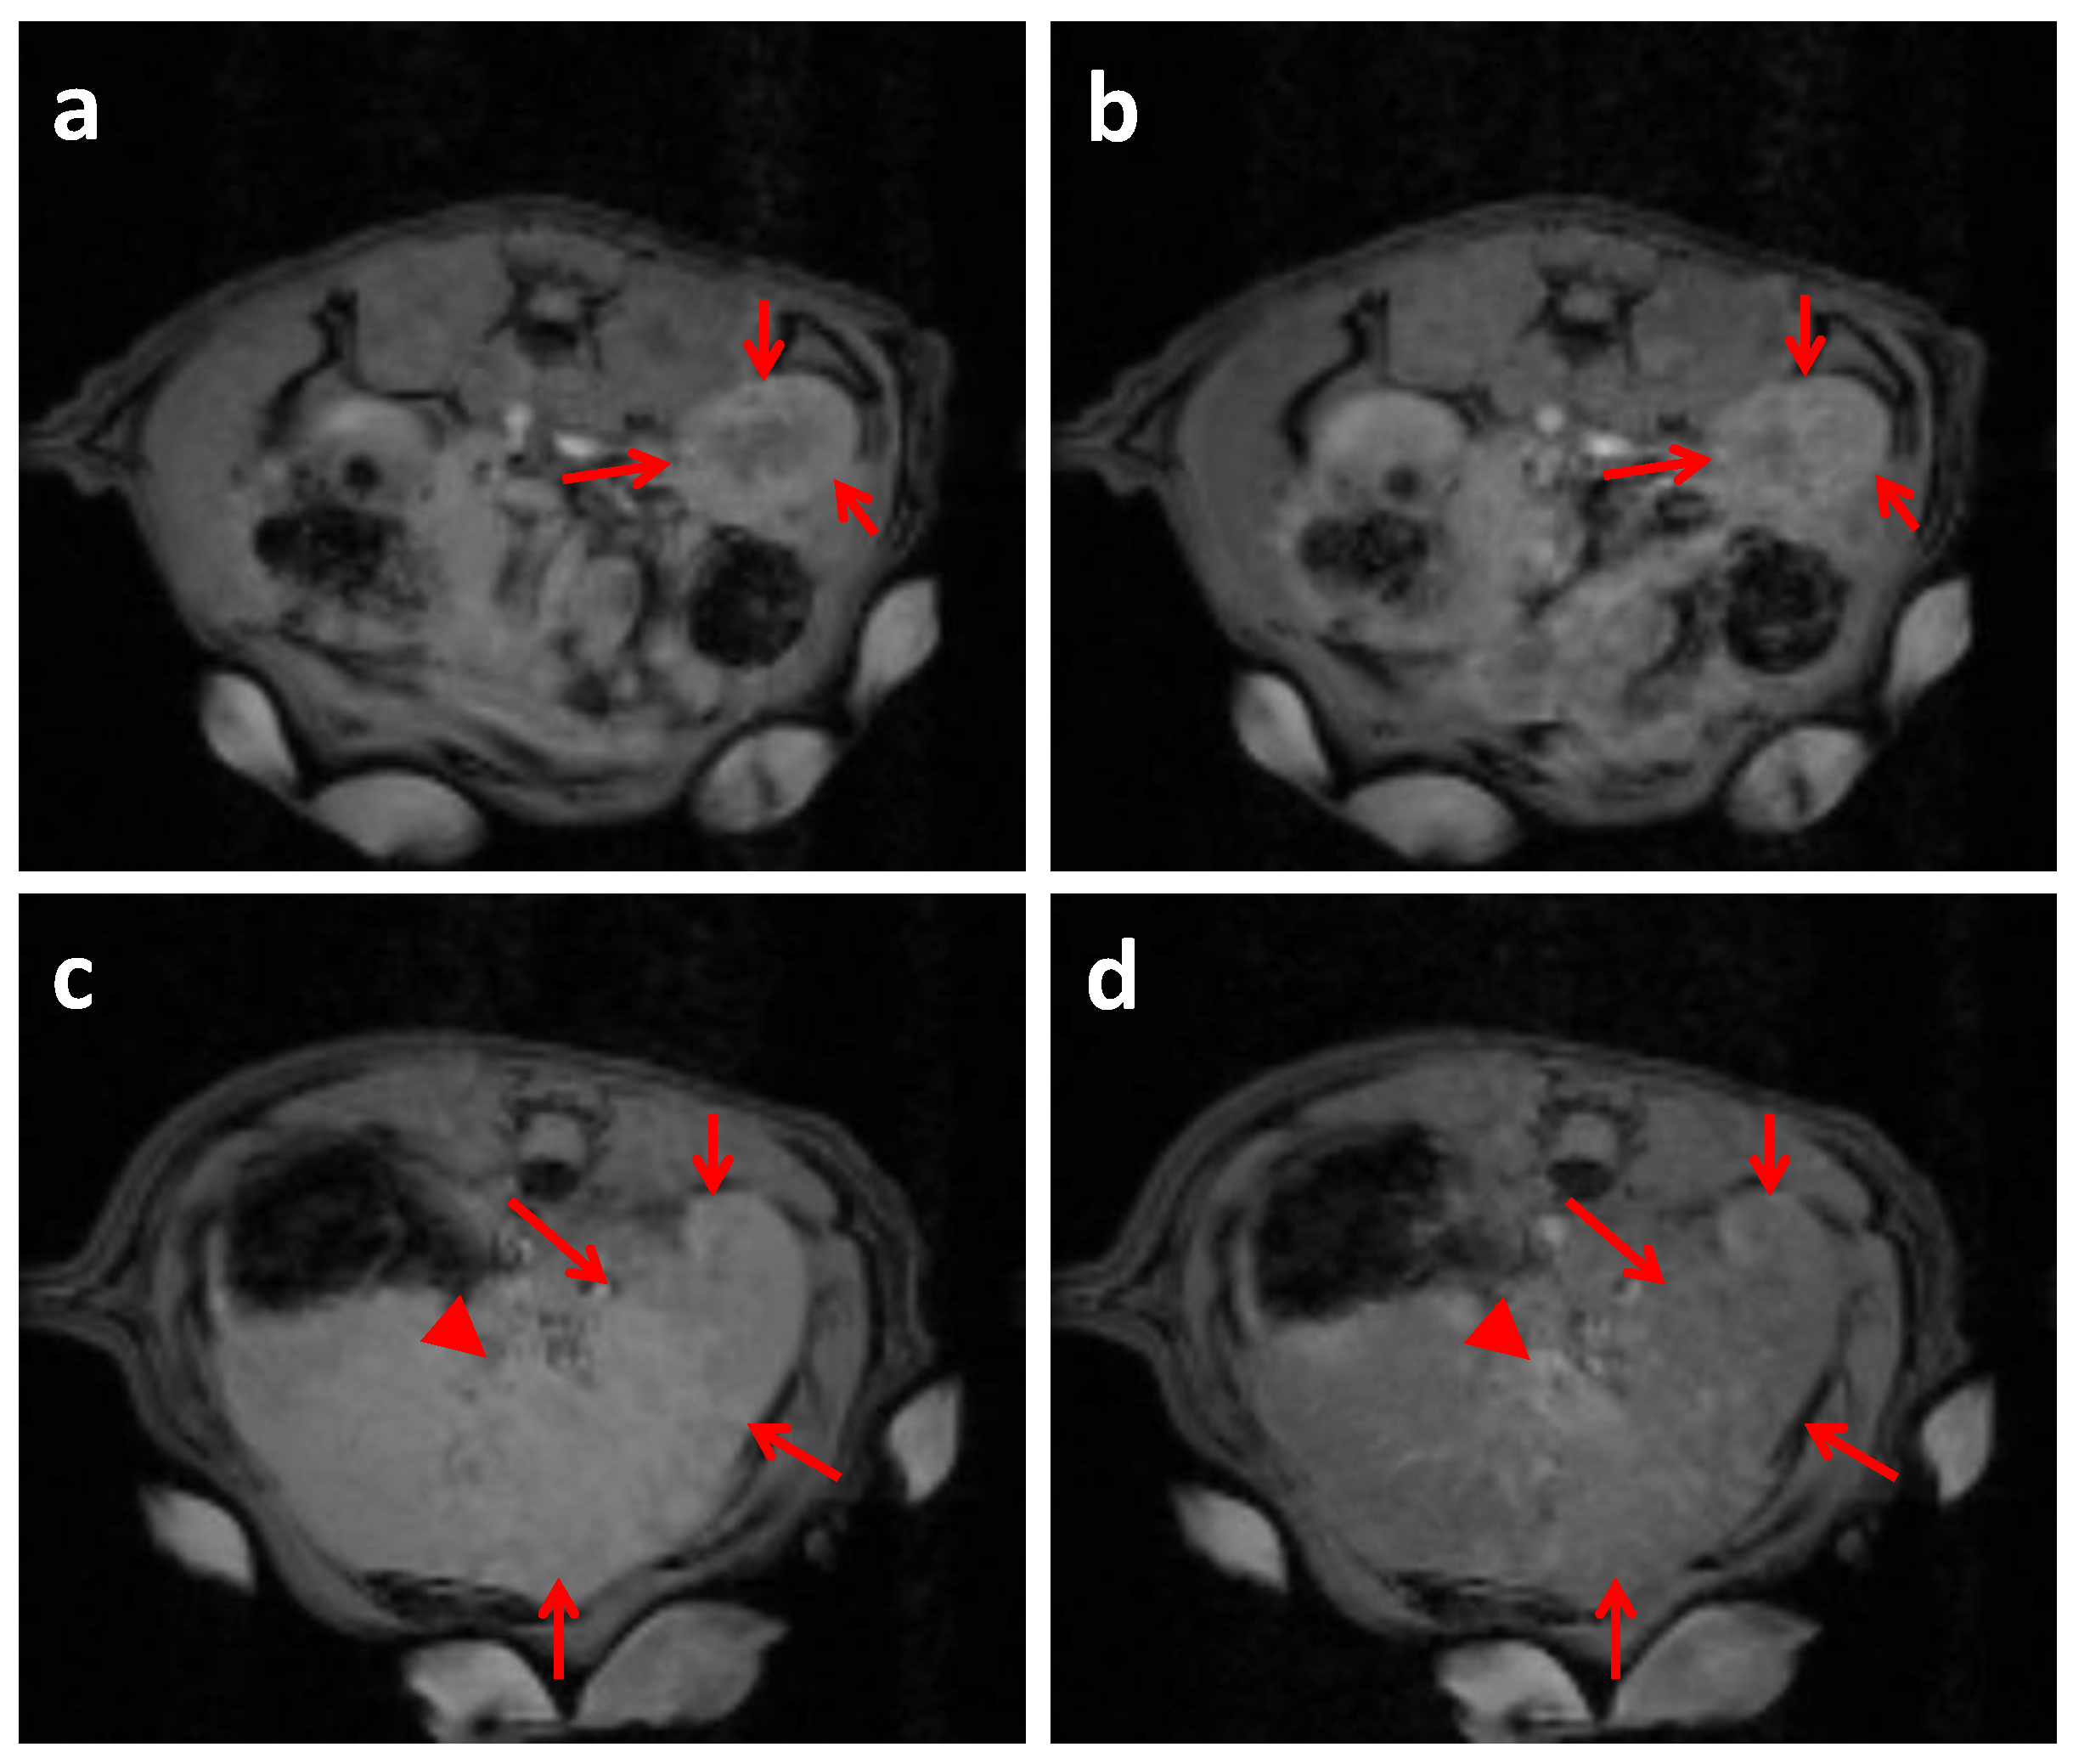

2.4. In Vivo MRI Studies Imaging

3.8. In Vivo MRI Studies Imaging